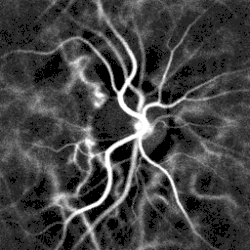

Pulsatile retinal blood flow in the optic nerve head region revealed by laser Doppler imaging[71]

Pulse oximetry of the finger and laser Doppler imaging of the eye fundus are often used in the clinics. Those techniques can assess the heart rate by measuring the delay between pulses.